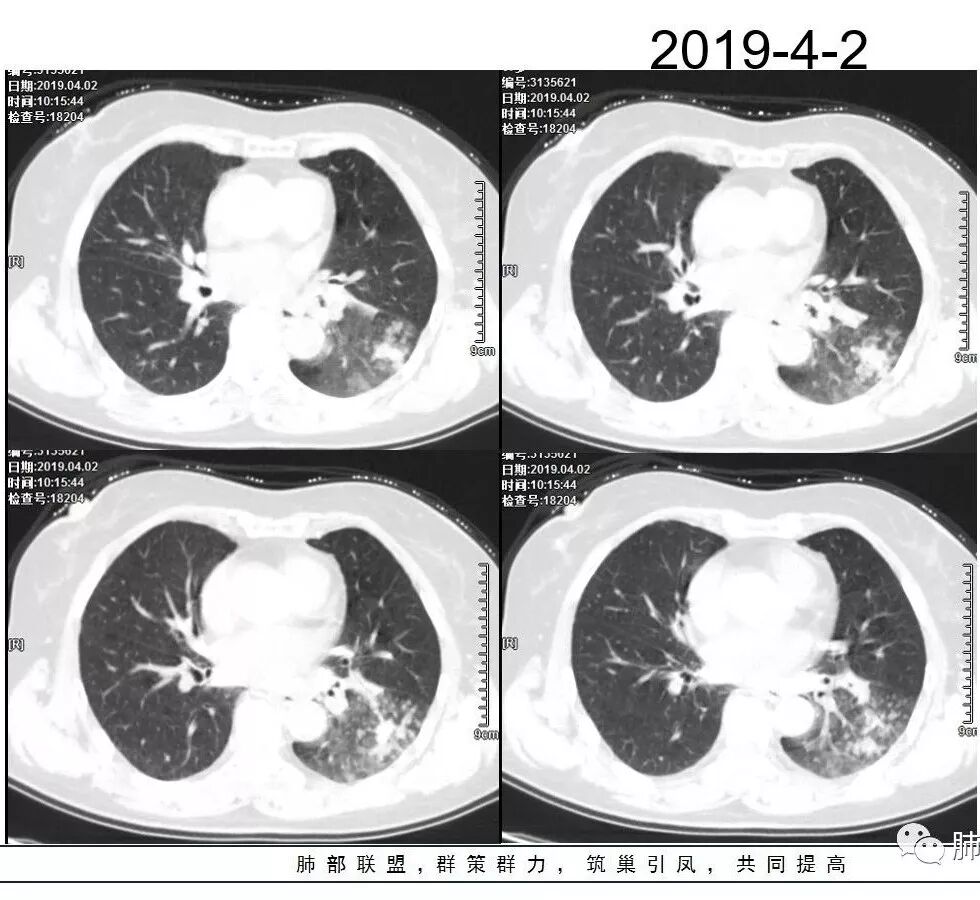

1、主病灶  左下叶斑片状、大片状致密影

2、两肺马赛克灌注

3、两侧肺门区钙化淋巴结

总共就这三大块

这三幅图是连续的,我们看到支气管中间这一幅狭窄了

大——小——大,狭窄后扩张

从这幅图看好像与周围病灶分界不清,支气管腔狭窄后扩张,支持炎性